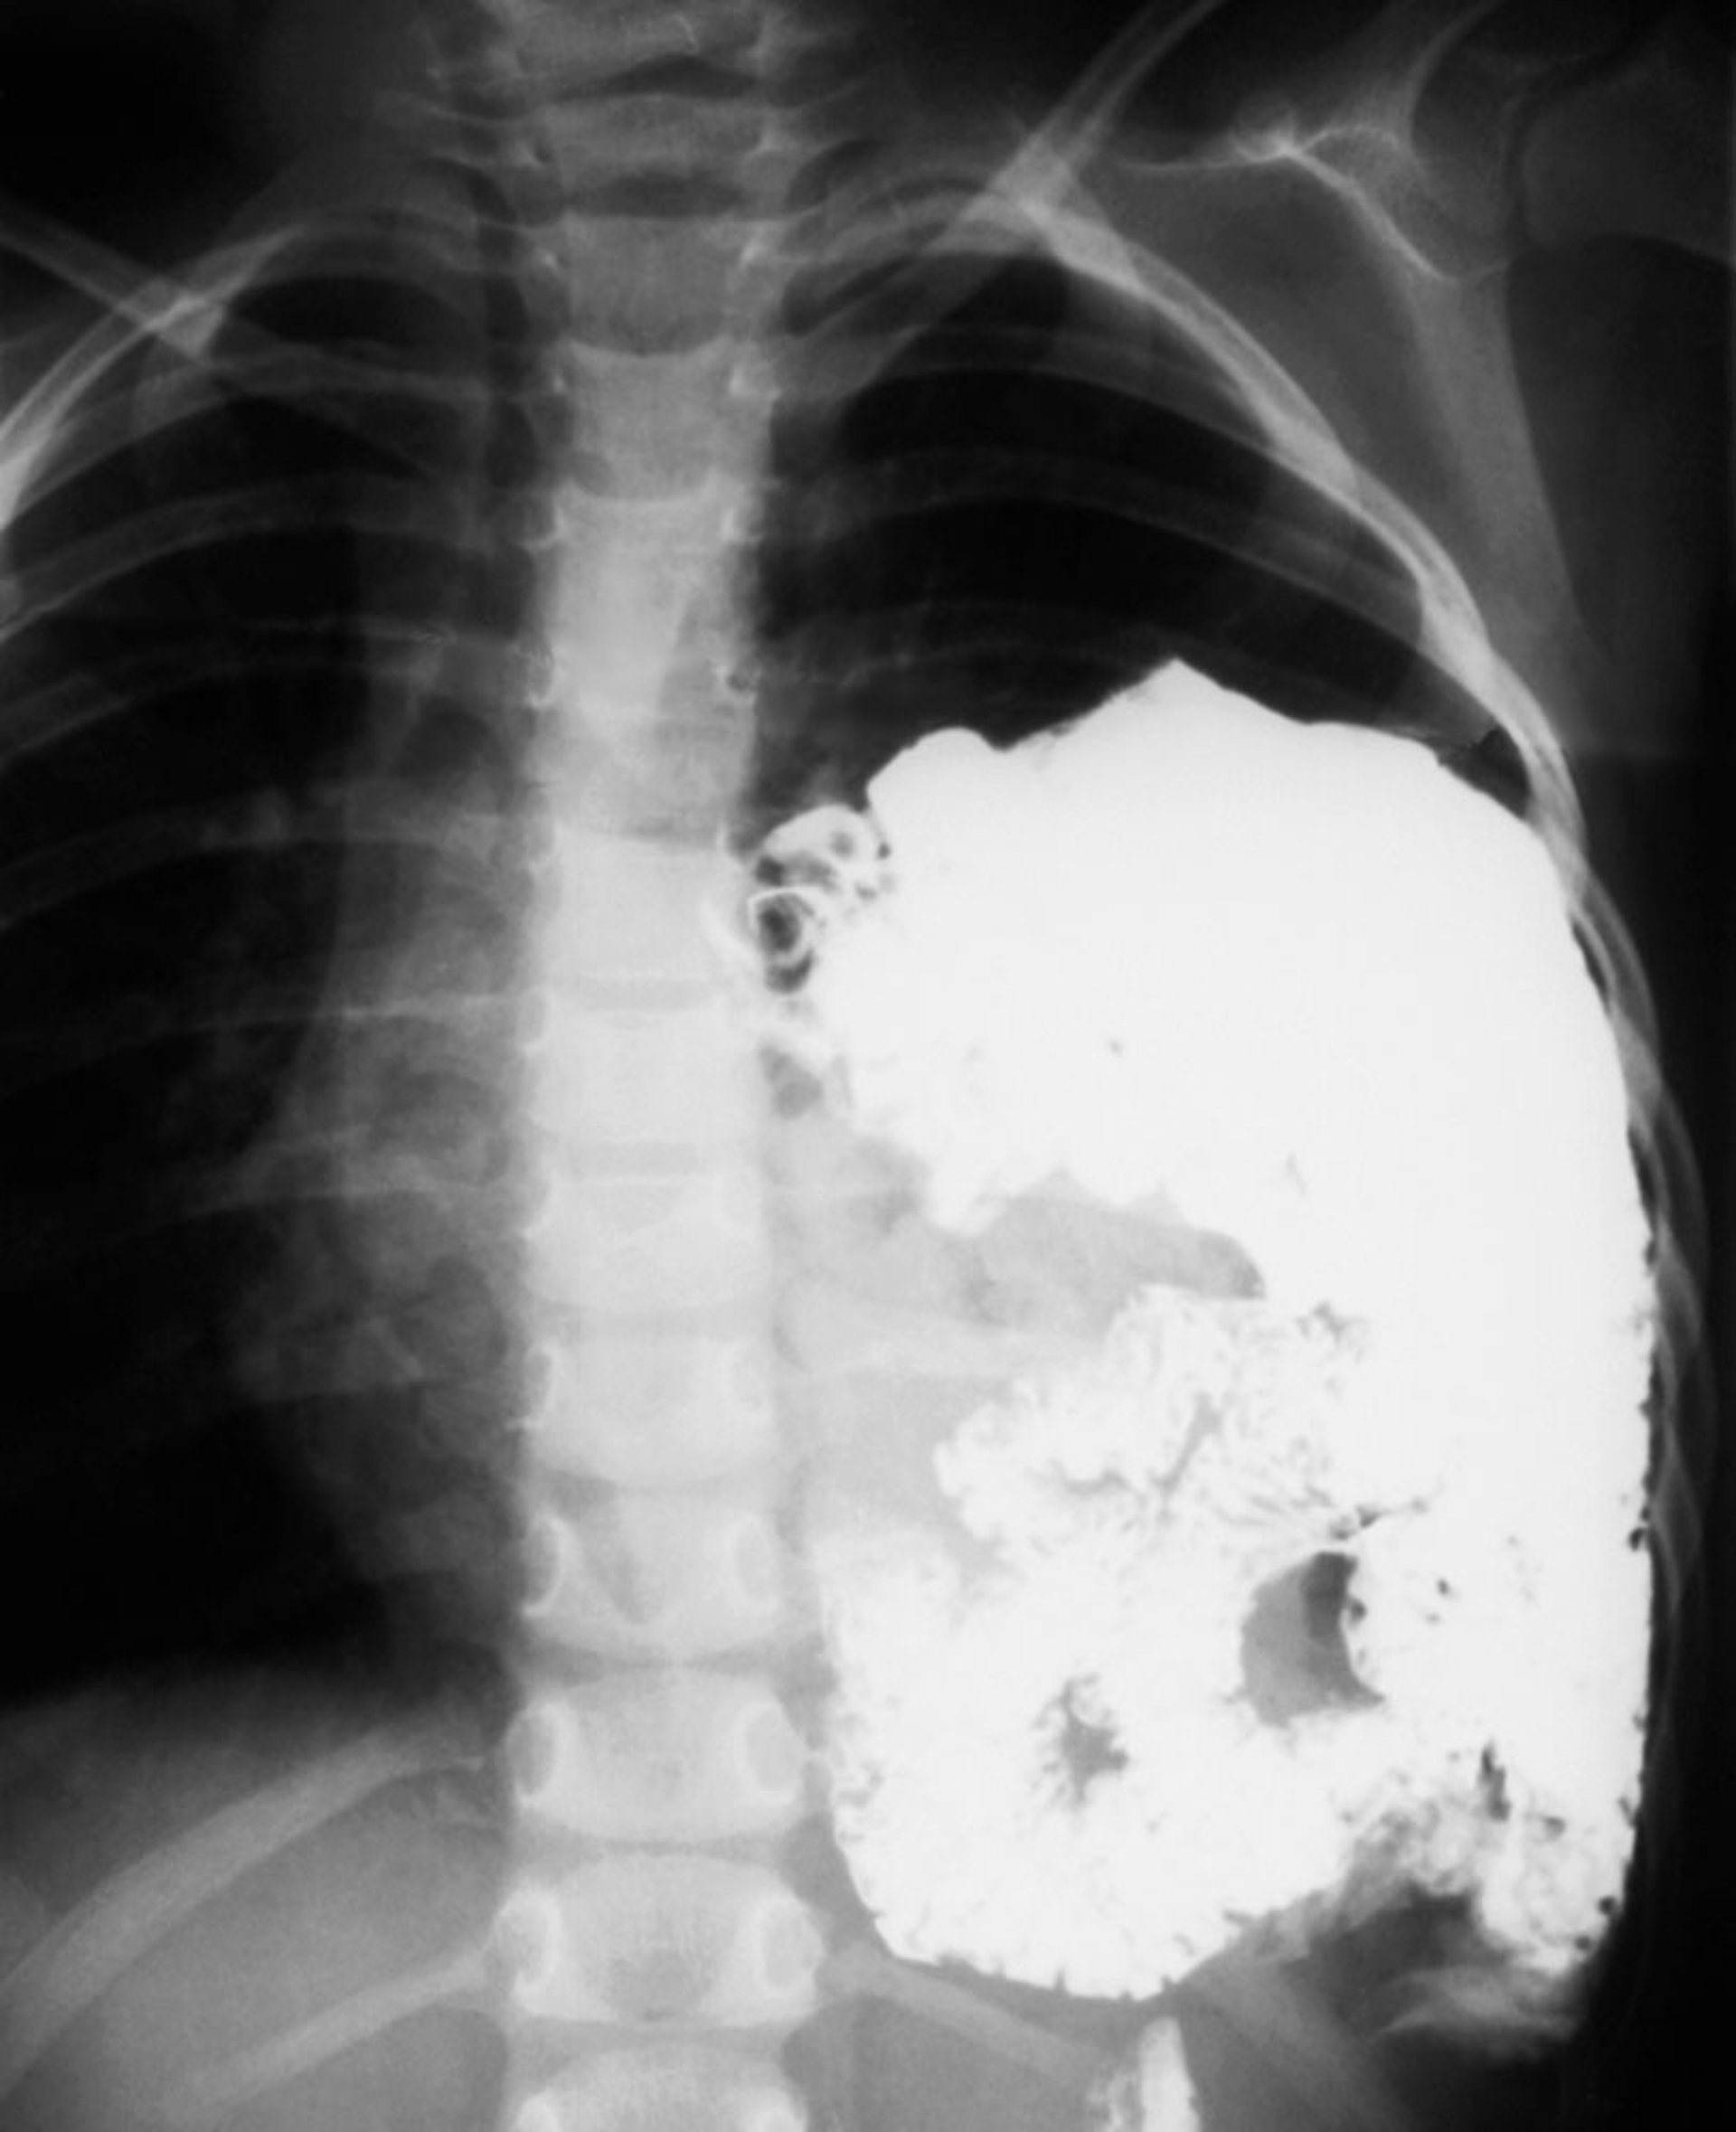

Thoát vị cơ hoành (1)

Phim chụp X-quang này cho thấy tình trạng thoát vị cơ hoành bẩm sinh ở trẻ sơ sinh. Các quai ruột lồi vào ngực trái (bên phải ảnh chụp X-quang).

Sau khi sinh, đưa ra chẩn đoán bằng phim chụp X-quang ngực cho thấy dạ dày và ruột lồi vào ngực. Trong một khiếm khuyết lớn, có rất nhiều không khí chứa đầy trong các quai ruột làm đầy lồng ngực cùng bên và chuyển vị cấu trúc tim và trung thất sang bên đối diện. Nếu chụp X-quang ngay sau khi sinh, trước khi trẻ sơ sinh nuốt không khí, các bộ phận trong bụng sẽ xuất hiện như một khối u mờ đục không có không khí ở nửa lồng ngực.